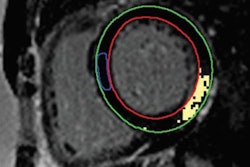

Comparison of heart muscle displacement in the left ventricles of three patients (V6, V10, V16) as calculated on 3D MRI. Image courtesy of the WMG at the University of Warwick.

Comparison of heart muscle displacement in the left ventricles of three patients (V6, V10, V16) as calculated on 3D MRI. Image courtesy of the WMG at the University of Warwick.Overall, the researchers found that the median heart muscle tracking error of their 3D MRI technique was 1.49 mm, which falls within the standard range of errors reported in the literature. In terms of maximum tracking error, the new technique proved to be even more accurate than standard techniques -- averaging a maximum error that was roughly 24% lower than the average maximum tracking error reported in the literature.